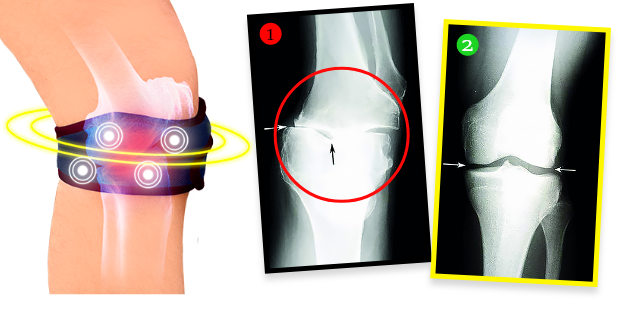

Pani Helena zrobiła po kuracji badanie RTG i okazało się, że zmiany zwyrodnieniowe w kolanie całkowicie się cofnęły! Lekarz osłupiał – nie wiedział, co powiedzieć. A fakty są takie, że dzięki biomagnetycznej opasce stan kolana pani Heleny nie tylko przestał się pogarszać. Tkanka chrzęstna i delikatne struktury w obrębie stawu zregenerowały się, a kolano wróciło do całkowitej sprawności sprzed lat. Opaska emituje bowiem naturalne i bezpieczne pole biomagnetyczne, które przenika w najgłębsze tkanki stawu, odżywiając i regenerując chrząstkę, przywracając jej elastyczność i sprężystość, a także stymuluje produkcję mazi stawowej, która amortyzuje i chroni przed bolesnym tarciem podczas poruszania się. Jest to terapia w pełni bezinwazyjna i bezpieczna.

Jeszcze 1,5 miesiąca temu miałem zniszczone, trzeszczące stawy, przez co ledwo chodziłem. Każdy większy wysiłek fizyczny sprawiał, że stawy eksplodowały bólem. Dzięki tej opasce czuję, że moje stawy są sprawne jak u nastolatka! Potwierdzają to wyniki kontrolnych badań RTG, USG i rezonansu magnetycznego. Kiedy je zobaczyłem, popłakałem się ze szczęścia. Ale kto by nie płakał? Moje kolana są jak nowe!”